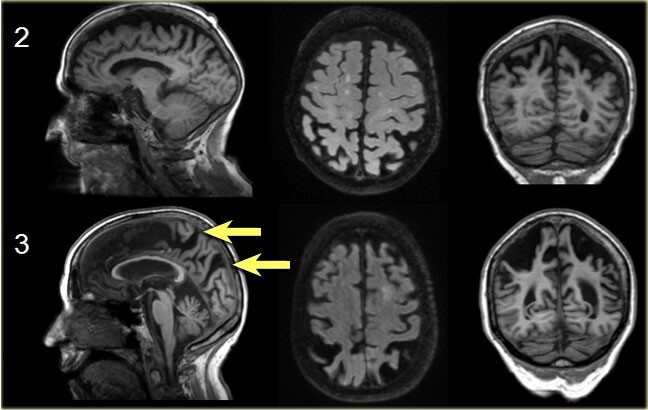

4)Шкала Коэдама (Koedam), используемая для оценки теменной атрофии при атипичной форме болезни Альцгеймера или ранним началом данного заболевания

Необходимо выполнить сканирование в 3 плоскостях для оценки анатомических структур:

1. сагиттальная проекция:

задняя часть поясной борозды,

теменно-затылочная борозда,

преклиновидная извилина;

2. корональная проекция:

теменная извилина;

3. аксиальная проекция:

теменные доли.

Подсчет в баллах (от 0 до 3) на основании выявленных отклонений:

Степень 0: борозды маленькие, нет атрофии извилин;

Степень 1: умеренное расширение борозд, умеренная атрофия извилин;

Степень 2: существенное расширение борозд и атрофия извилин;

Степень 3: еще большее расширение борозд, атрофия извилин по типу «лезвие ножа».